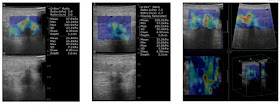

Ultrasound detected incidentally an upper pole renal cystic lesion # 13x23mm in B mode with aliasing sign on Doppler ultrasound.  RI = 0.3-0.5 and V= 130-230 cm/sec. It maybe an intrarenal AVM.

MSCT confirmed an intrarenal AVM that created an intrarenal aneurysm and managed stenting successfully the AVM.

Doppler ultrasound could differentialize an intrarenal aneurysm from a renal cystic lesion while B mode ultrasound could not to do.